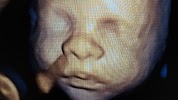

Sweet Baby Face

Referred a customer to them and they were very accommodating. She sent me the 3d pictures and they were beautiful.

The images are so cool. Plus the staff is so sweet! I did the 9 week gender blood test then I had an ultrasound. The 3d 4d images are stunning. I drove an hour away because I heard sweet baby face was the best Ultrasound facility in Kentucky.

Such a fun experience. I loved the 3D4D images. We drove 2 hours away because we heard this was the very best place to get a hd 3d 4d ultrasound and we were not disappointed. The tech was so sweet and spent extra time trying to get the baby to move. We had a lot of family members with us and there was so much room. We will be coming up here again. I wish we would have came for the 9 week gender.

Love the 3d4d ultrasounds! They are so sweet ! The only place in Kentucky to get a ultrasound!

Best 3d4d in Kentucky. Very friendly staff and you can find gender as early as 9 weeks!

The Best HD 3D/4D Ultrasounds around Kentucky. I enjoyed the experience and my images were awesome.

BEST PLACE!!!! THE ULTRASOUNDS HERE ARE AMAZING!!! I was blown away by the HD ultrasound! We also found out gender at 9 weeks here too!